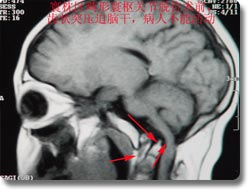

开展了脑内各部位肿瘤的显微手术治疗,尤其是经口鼻蝶入路作垂体瘤切除术、听神经瘤、斜坡脊索瘤、脑膜瘤、天幕、岩尖、鞍结节、海绵窦、脑膜瘤,颅鼻沟通瘤、跨前颅凹、中颅凹沟通瘤、跨后颅凹中颅凹沟通瘤、脑干肿瘤等多种疑难复杂的颅底肿瘤的显微手术治疗,手术成功率、肿瘤全切率、颅神经的保全率等均处于国内先进水平。并开展了寰枕区畸形寰枢关节脱位经口斜坡和切除等多种高难度手术,确立了神经外科在颅底手术领域的国内领先地位。颅底外科中经口、上颌骨劈开入路进行下斜坡、颅颈联合区的手术达到国际水平。